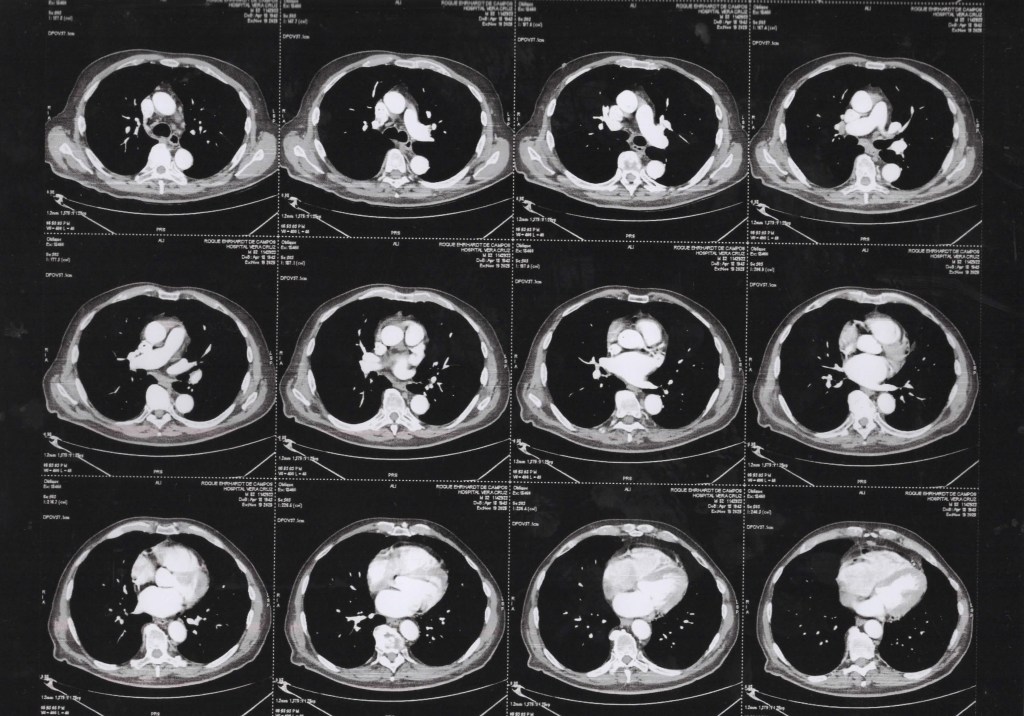

TCM Torax 19 11 2025 janela de mediastino/tecidos moles.